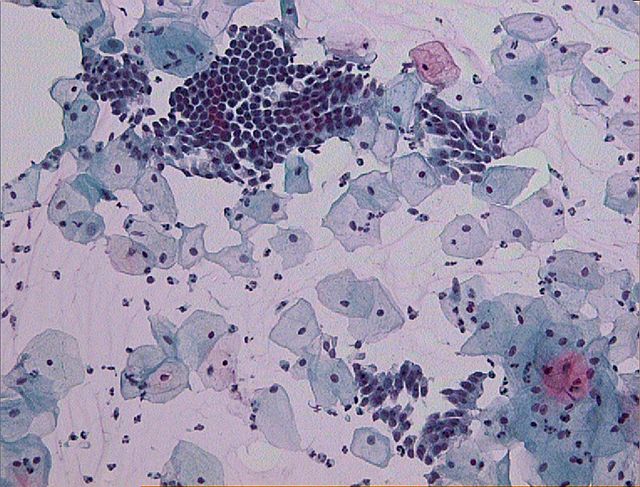

Kitajska raziskovalna skupina je z analizo DNK brisov materničnega vratu določila vrstno sestavo bakterij, ki so bile del vaginalne mikrobiote pri 45 neokuženih in 90 ženskah, okuženih s HPV. Izkazalo se je, da več ni vedno bolje. Kitajske znanstvenice in znanstveniki so najmanjšo vrstno pestrost določili v mikrobioti neokuženih žensk. Vrstna pestrost je bila višja pri posameznicah s trajno okužbo v primerjavi s posameznicami s prehodno okužbo.

Pri neokuženih v mikrobioti dominira ena bakterija iz rodu Lactobacillus. Znano je, da laktobacíli vzdržujejo nizek pH v nožnici, kar otežuje naselitev drugih bakterij, pa tudi okužbo celic povrhnjice materničnega vratu z virusom HPV. Pri dobri polovici okuženih posameznic je kitajska raziskovalna skupina odkrila, da je dominantna vrsta bakterije prav tako iz rodu Lactobacillus. Pri ostalih okuženih pa je bila dominantna bakterijska vrsta iz drugega rodu, predvsem Sneathia in Prevotella

Vir slike: https://upload.wikimedia.org/wikipedia/commons/thumb/d/d6/Pap_test_wnl…